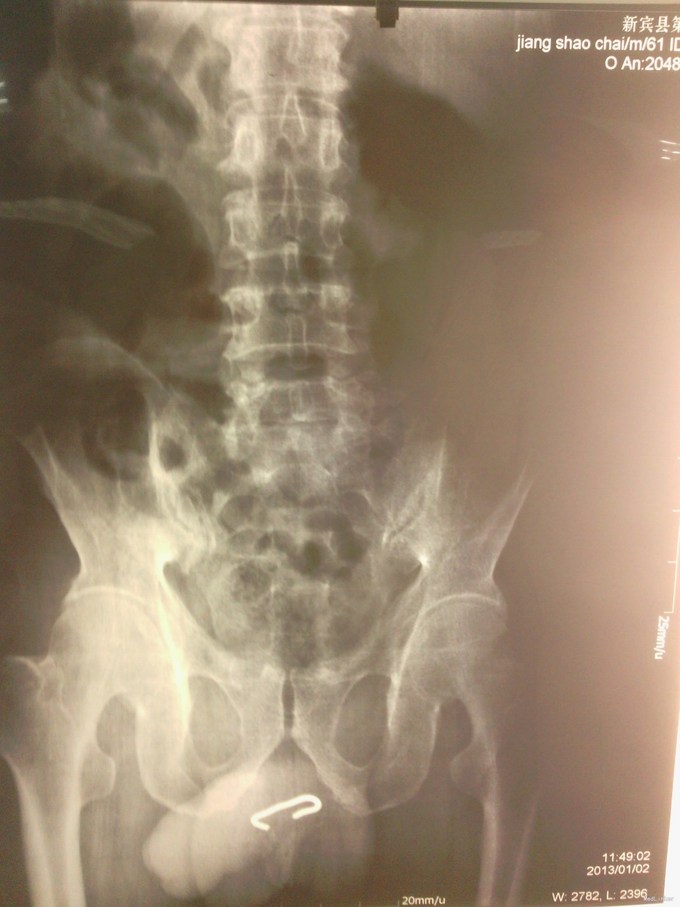

性别 : 男 年龄 :60岁 一、病例特点 : 1.主诉:发现阴茎阴囊肿水肿1天。 2.现病史:患者弟弟1天前发现患者阴茎阴囊水肿,患者智力障碍,家属反复问其原因后自诉尿道内放置铁丝,家属估计留置2天余。就诊于新宾县二院排X片显示双J型直径4mm铁丝。长约4cm。位于前尿道。建议上级医院治疗,遂就诊于本院急诊,来我科后试行弯钳取异物失败,告知患者家属应需手术治疗,患者家属拒绝,后又返院接受手术取出异物。急诊给予患者手术治疗。 3.既往史:肛门塞异物手术取出术后3次,否认高血压糖尿病冠心病,否认输血史。 否认过敏史。

尿道异物 尿道切开异物取出+输尿管镜尿道探查+膀胱切开造瘘术 手术简要经过 : 尿道切开,取出异物,留置导尿管困难,行输尿管镜探查,因炎症重,输尿管镜无法探及尿道,给予膀胱切开留置尿管,留置膀胱造瘘管。 麻醉成功后,取结石位,常规消毒,铺无菌巾。见阴茎、会阴部肿胀明显、可及瘀斑。阴茎根部可及异物。长约4厘米左右,阴茎及会阴部质硬感。在阴茎腹侧可及异物中线处,逐层切开。见阴茎皮肤水肿明显,适当分离尿道,见尿道水肿明显,苍白,血运欠佳。将尿道切开约3厘米,小心分离异物。将异物完整取出,见异物为硬性钢条,长约4厘米,两头带钩型,钢条直径约0.4cm。试行经尿道外口留置尿管,因尿道被异物挫伤较重,无法找到正道,留置尿管未成功。试行应用输尿管镜探查尿道,见尿道球部水肿严重,炎症改变严重,无法找到正道。遂向患者家属交代,需切开膀胱。取下腹正中切口约4厘米,逐层切开腹壁各层,直达膀胱前间隙。将腹膜向上推开,打开膀胱前壁,吸净残尿。见膀胱内景混浊,双管口喷尿正常,膀胱壁炎症增厚,膀胱内未见占位病变,在手指指引下,试行从尿道外口下尿道探子,顺利进入膀胱,从膀胱内,在尿道探子指引下顺利留置F14硅胶尿管一枚,再在F14号尿管引导下顺利留置F18号尿管一枚。应用无菌生理盐水反复冲洗膀胱,仔细探查膀胱后。于膀胱壁上另戳孔留置F22号尿管一枚,充当膀胱造瘘管,固定好。关闭膀胱切口(3-0可吸收线连续全层缝合膀胱壁,3-0可吸收线连续加固浆肌层),确切,无尿外渗。探查膀胱切口无漏尿,无活动出血,膀胱造瘘管通畅,引出淡黄尿液。术区确切止血后,留置耻骨后引流一枚,清点器械纱布无误,逐层关闭上腹部切口。再以3-0可吸收线间断结节缝合尿道,确切。3-0可吸收线间断缝合阴茎皮下及皮肤。术毕。术中过程顺利,无副损伤。术中失血约20ml。未输血。切口辅料覆盖固定良好。阴茎部切口弹力绷带包扎固定良好。 术后患者恢复良好。